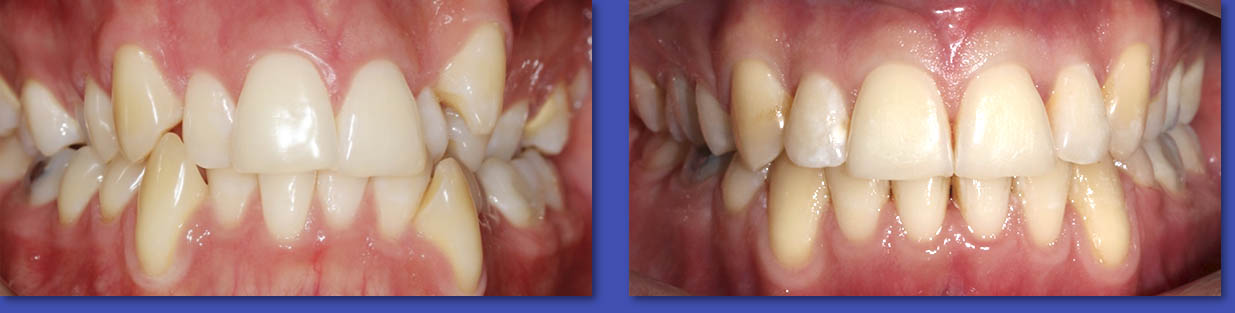

2. PERIODONCIA

La Periodoncia se dedica al tratamiento de las patologías que afectan a las encías y al hueso de soporte de los dientes. Las enfermedades principales son la Gingivitis y la Periodontitis, ambas se manifiestan principalmente por la inflamación y sangramiento de las encías. El tratamiento puede variar desde realizar una correcta técnica de cepillado y el uso de cinta dental, pasando por el destartraje (eliminación de sarro), o el pulido radicular en el caso de las periodontitis.

ANTES

DESPUÉS